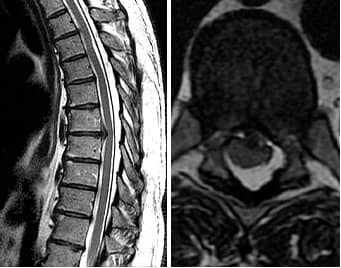

Discover the cause of your back pain with Lumbar MRI! Fast and reliable MRI imaging service with expert radiologists. Click for medical imaging center options.